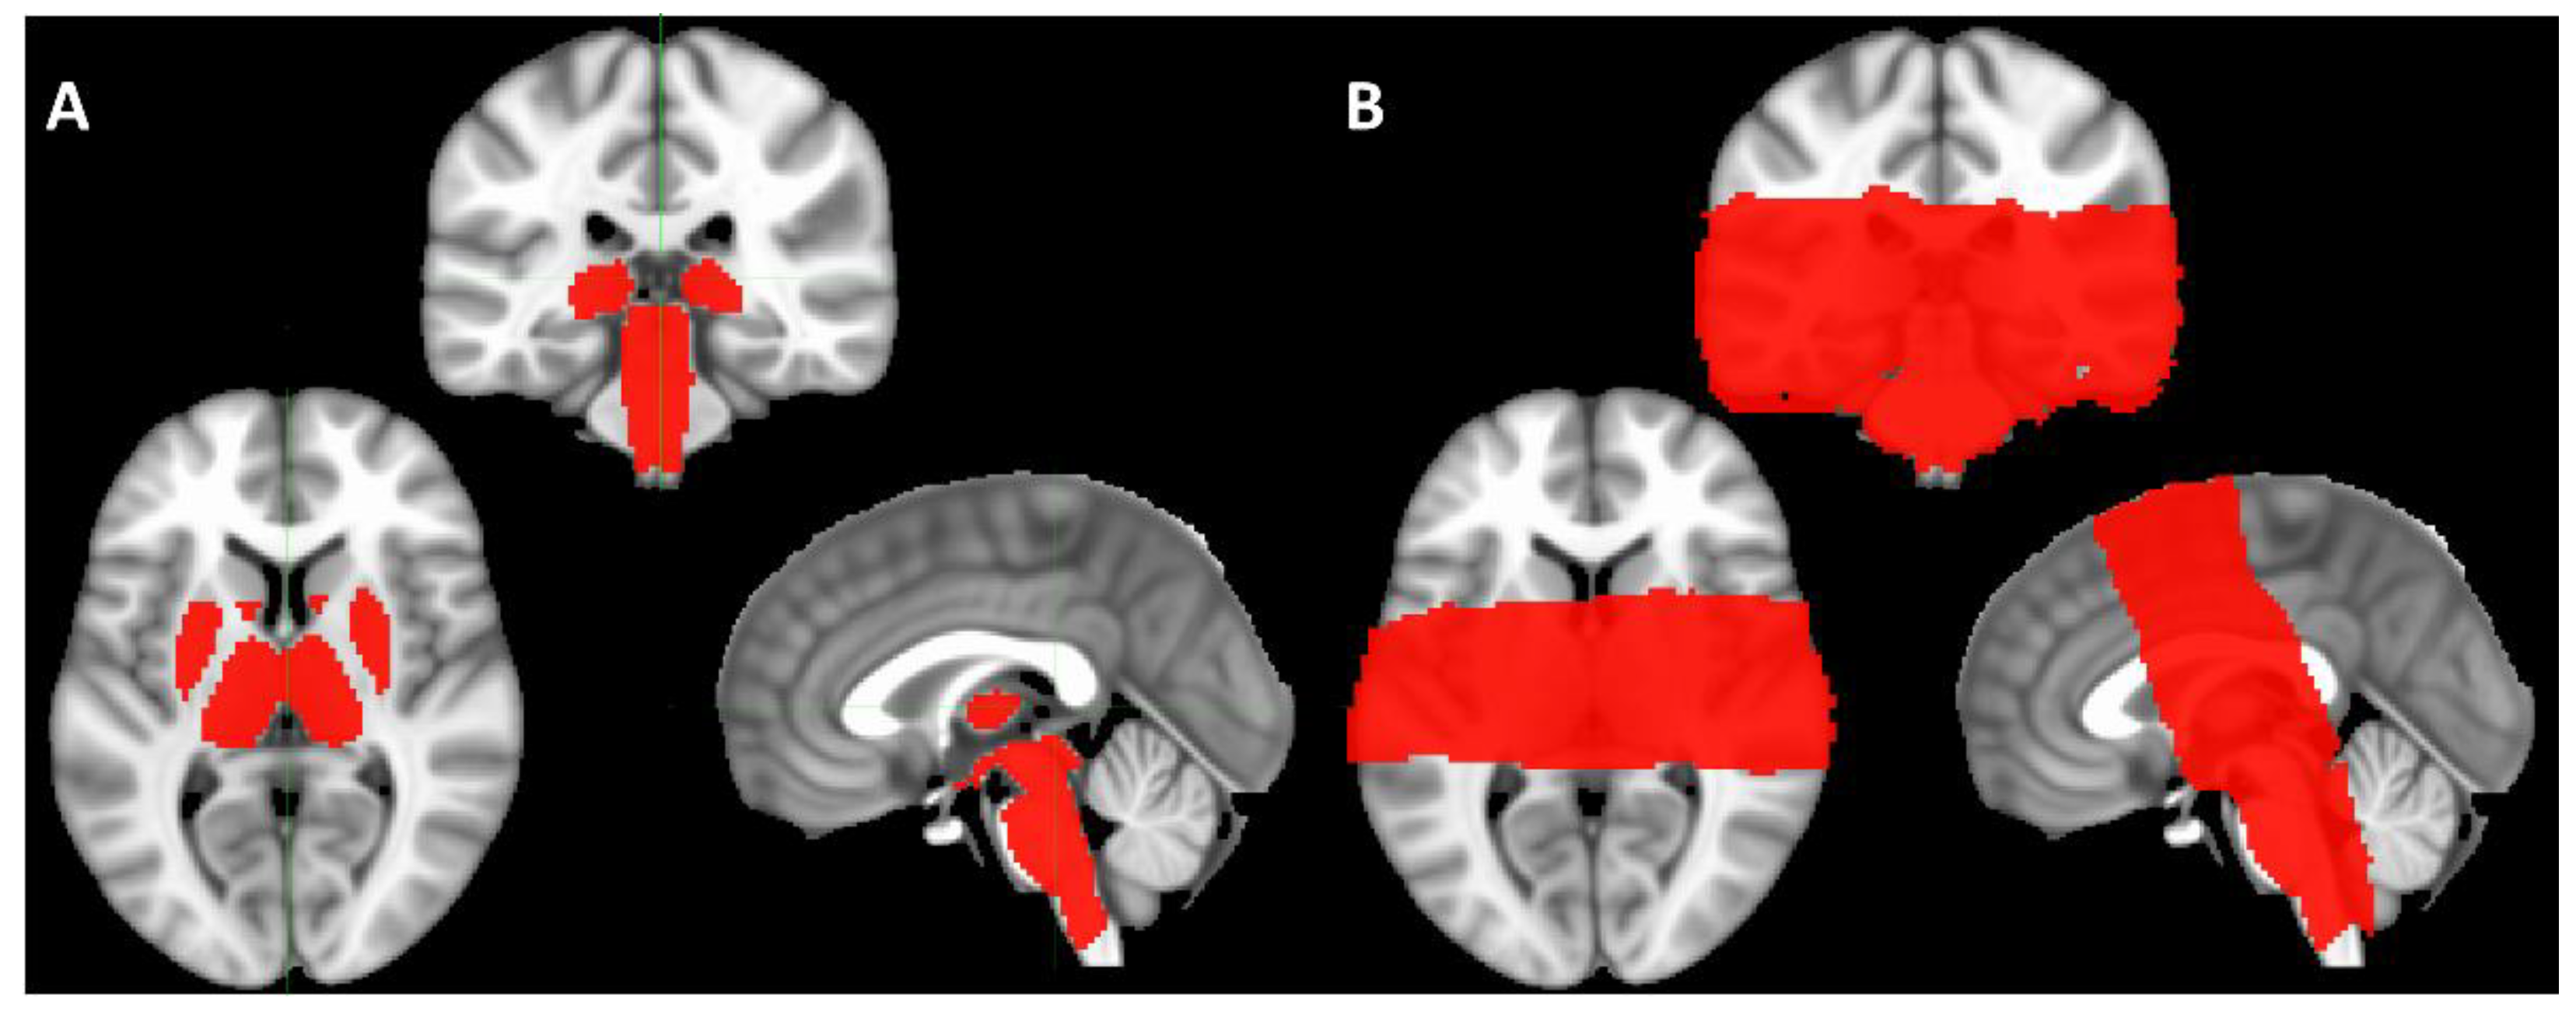

2. Materials and Methods